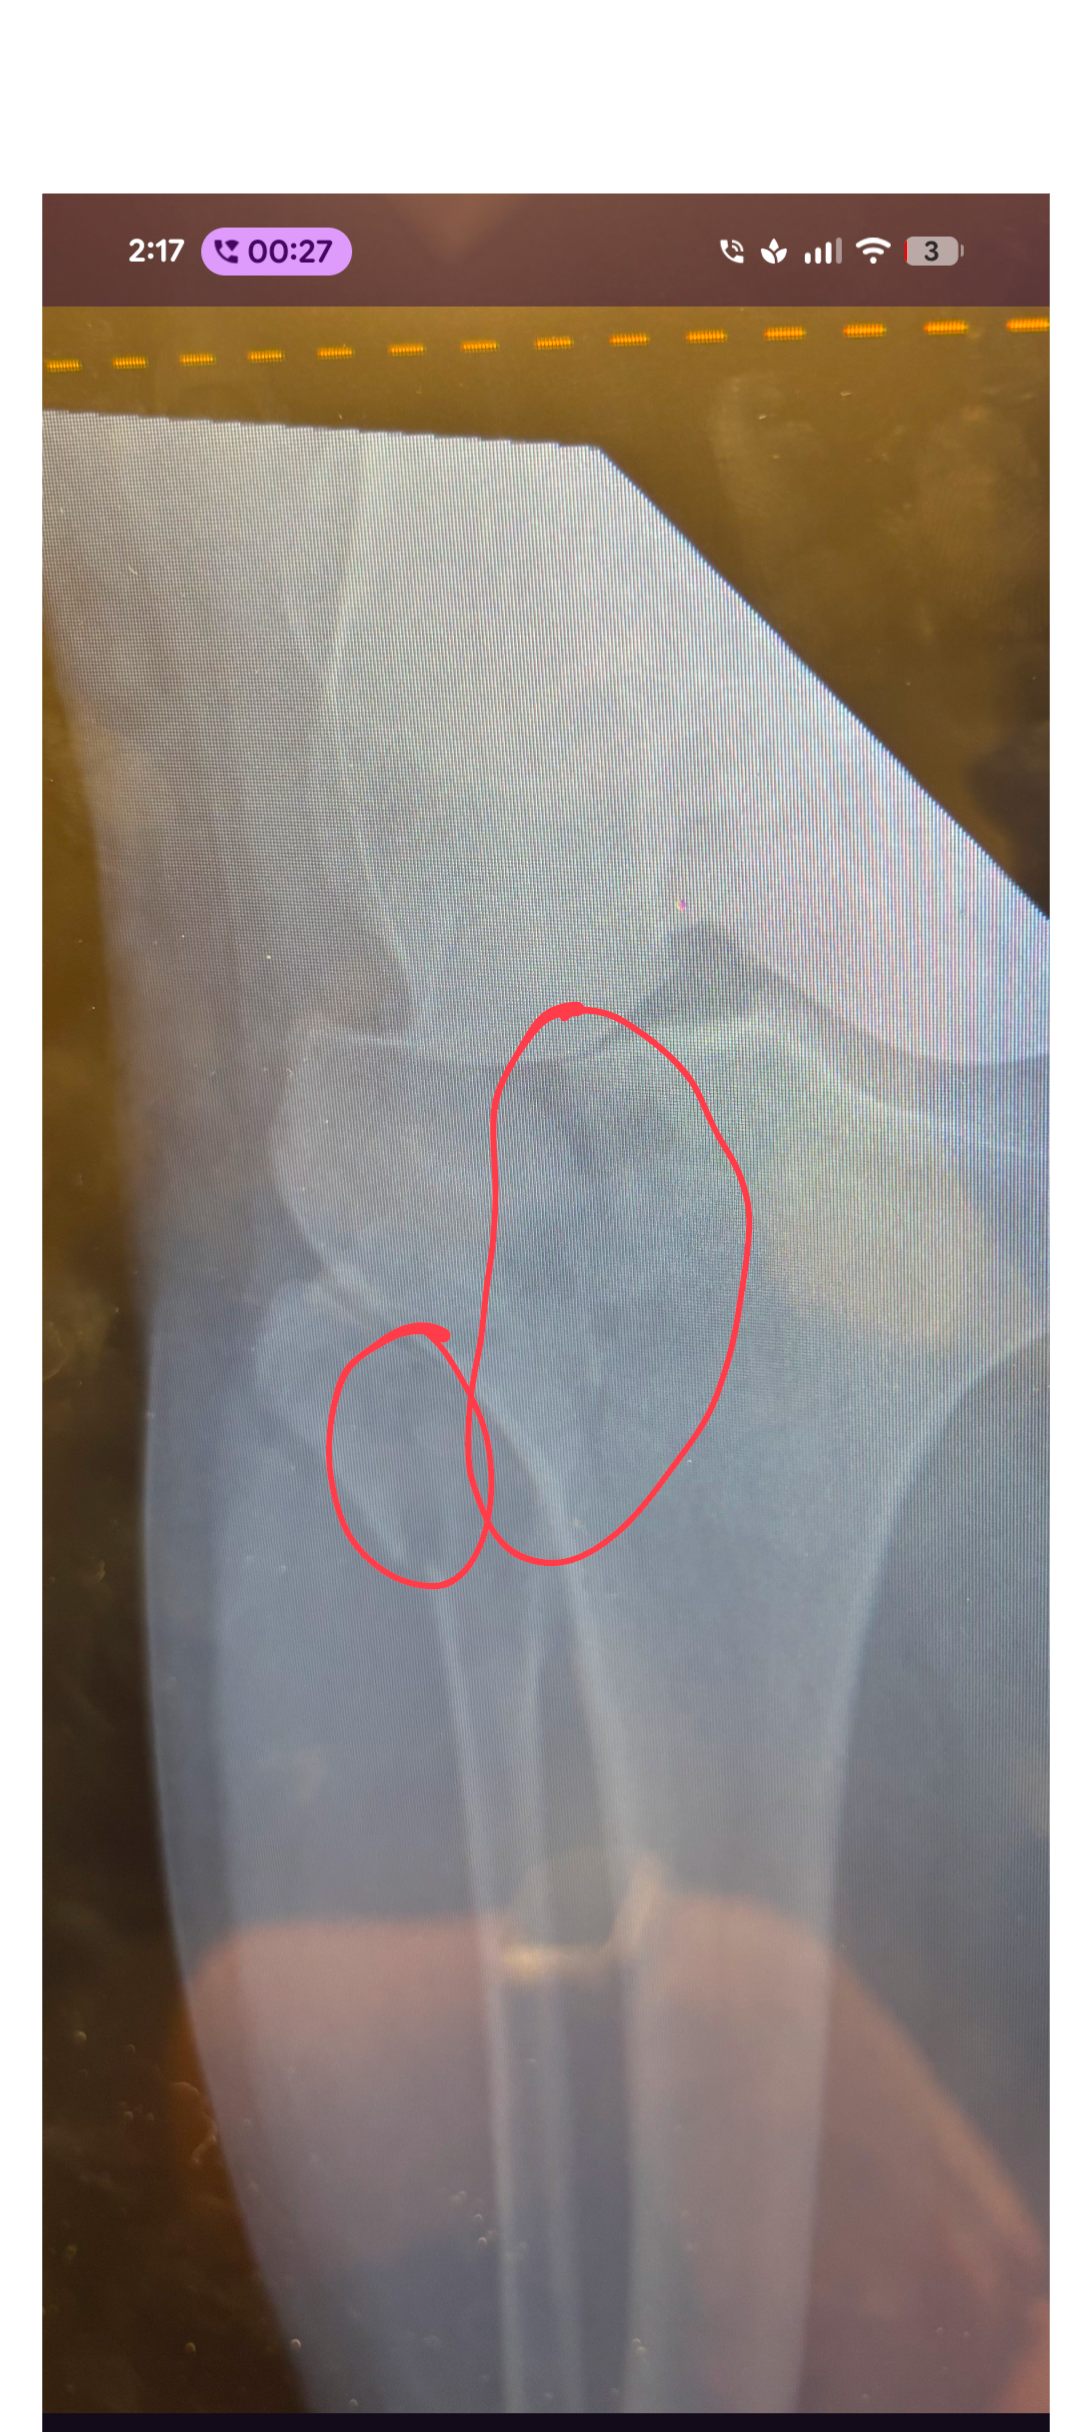

On New Year's Eve, my mom suffered a serious accident when she fell off a ladder and broke her leg. She underwent surgery on New Year's Day to repair the break, and now faces a long road to recovery. For the next three months, she is bedridden and unable to put any weight on her leg, with another surgery already planned and a total recovery time that could stretch to a year or more. She requires round the clock care for repositioning, toileting, and pain management. As her primary caregiver, I have had to put off working so I can be home to take care of her full-time. This has put us in a difficult financial position, as we are now falling behind each month while I am not working. I had a full time career lined up that we were going to transition to prior to the accident. However, now we're behind on overhead each month plus other expenses related to caring for my mom.